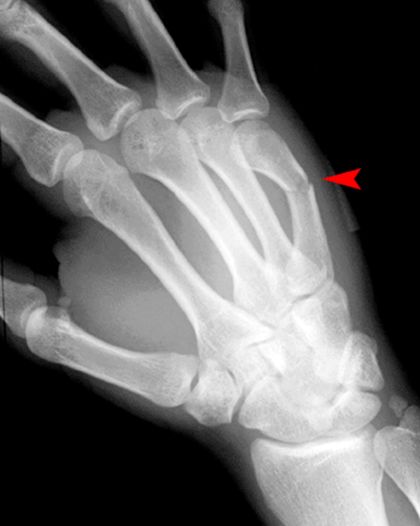

拳击手骨折

• 握拳撞击

• 通常发生在第五掌骨